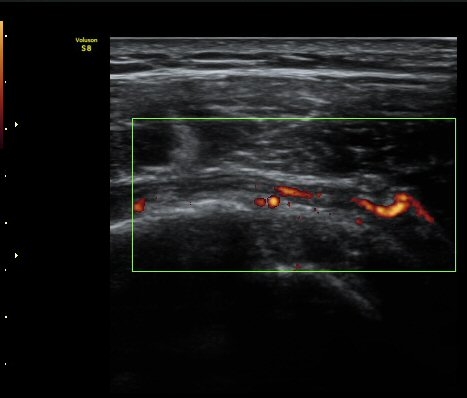

ÆÄ¿öµµÇ÷¯°Ë»ç¿¡¼­ ±Ø»ó°Ç°ú Á¡¾×³¶ÁÖÀ§¿¡¼­ ¼ö¾×Àú·ù°¡ °üÂûµÈ´Ù(±×¸² 6, 7).

ȸÀü±Ù°³°£°Ý(rotator cuff interval) Ⱦ´Ü¸é°Ë»ç¿¡¼­ Á¡¾×³¶¸Å ¼ö¾× Àú·ù°¡ °üÂûµÈ´Ù(±×¸² 1).

±Ø»ó°Ç Á¾´Ü¸é°Ë»ç¿¡¼­ Á¤¸Æ³¶³» ¼ö¾×Àú·ù¿Í ±Ø»ó°Ç³» ¼®È¸È­À½¿µÀÌ °üÂûµÈ´Ù(±×¸² 2, 3).